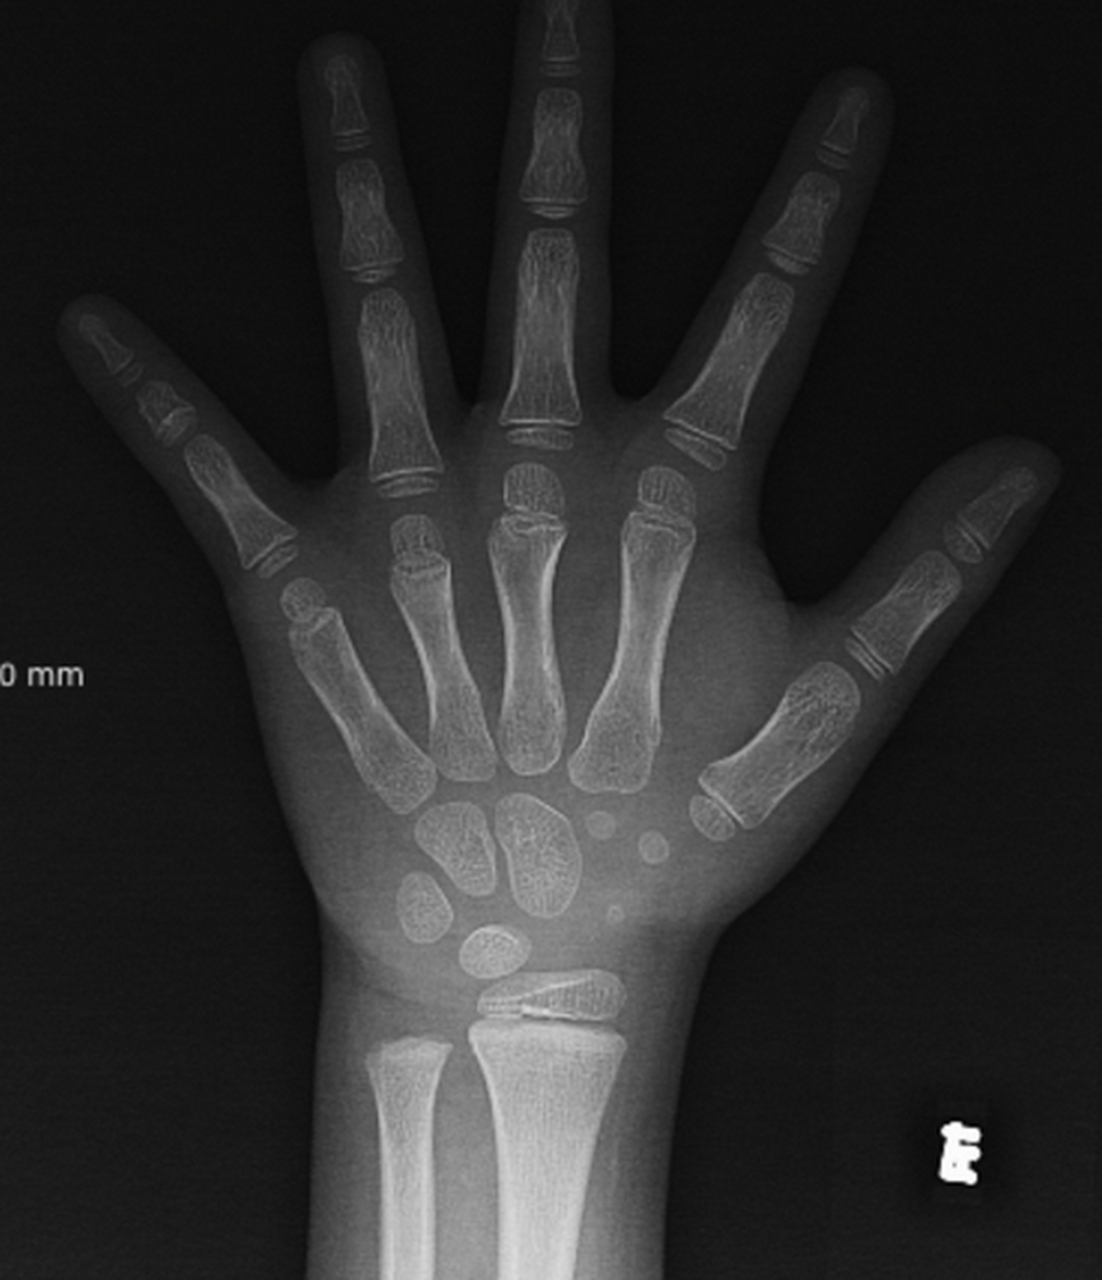

【病例讨论】看看这是几岁的骨龄 [病例帖]

14岁男孩骨龄16岁,还能长高多少?主要看骨骺线的闭合情况!

注意:一般女孩骨龄14岁,男孩骨龄16岁,骨骺线基本闭合,身高停止生长!

一般女孩骨龄达到14岁,男孩骨龄达到16岁,骨骺就接近闭合,停止生长